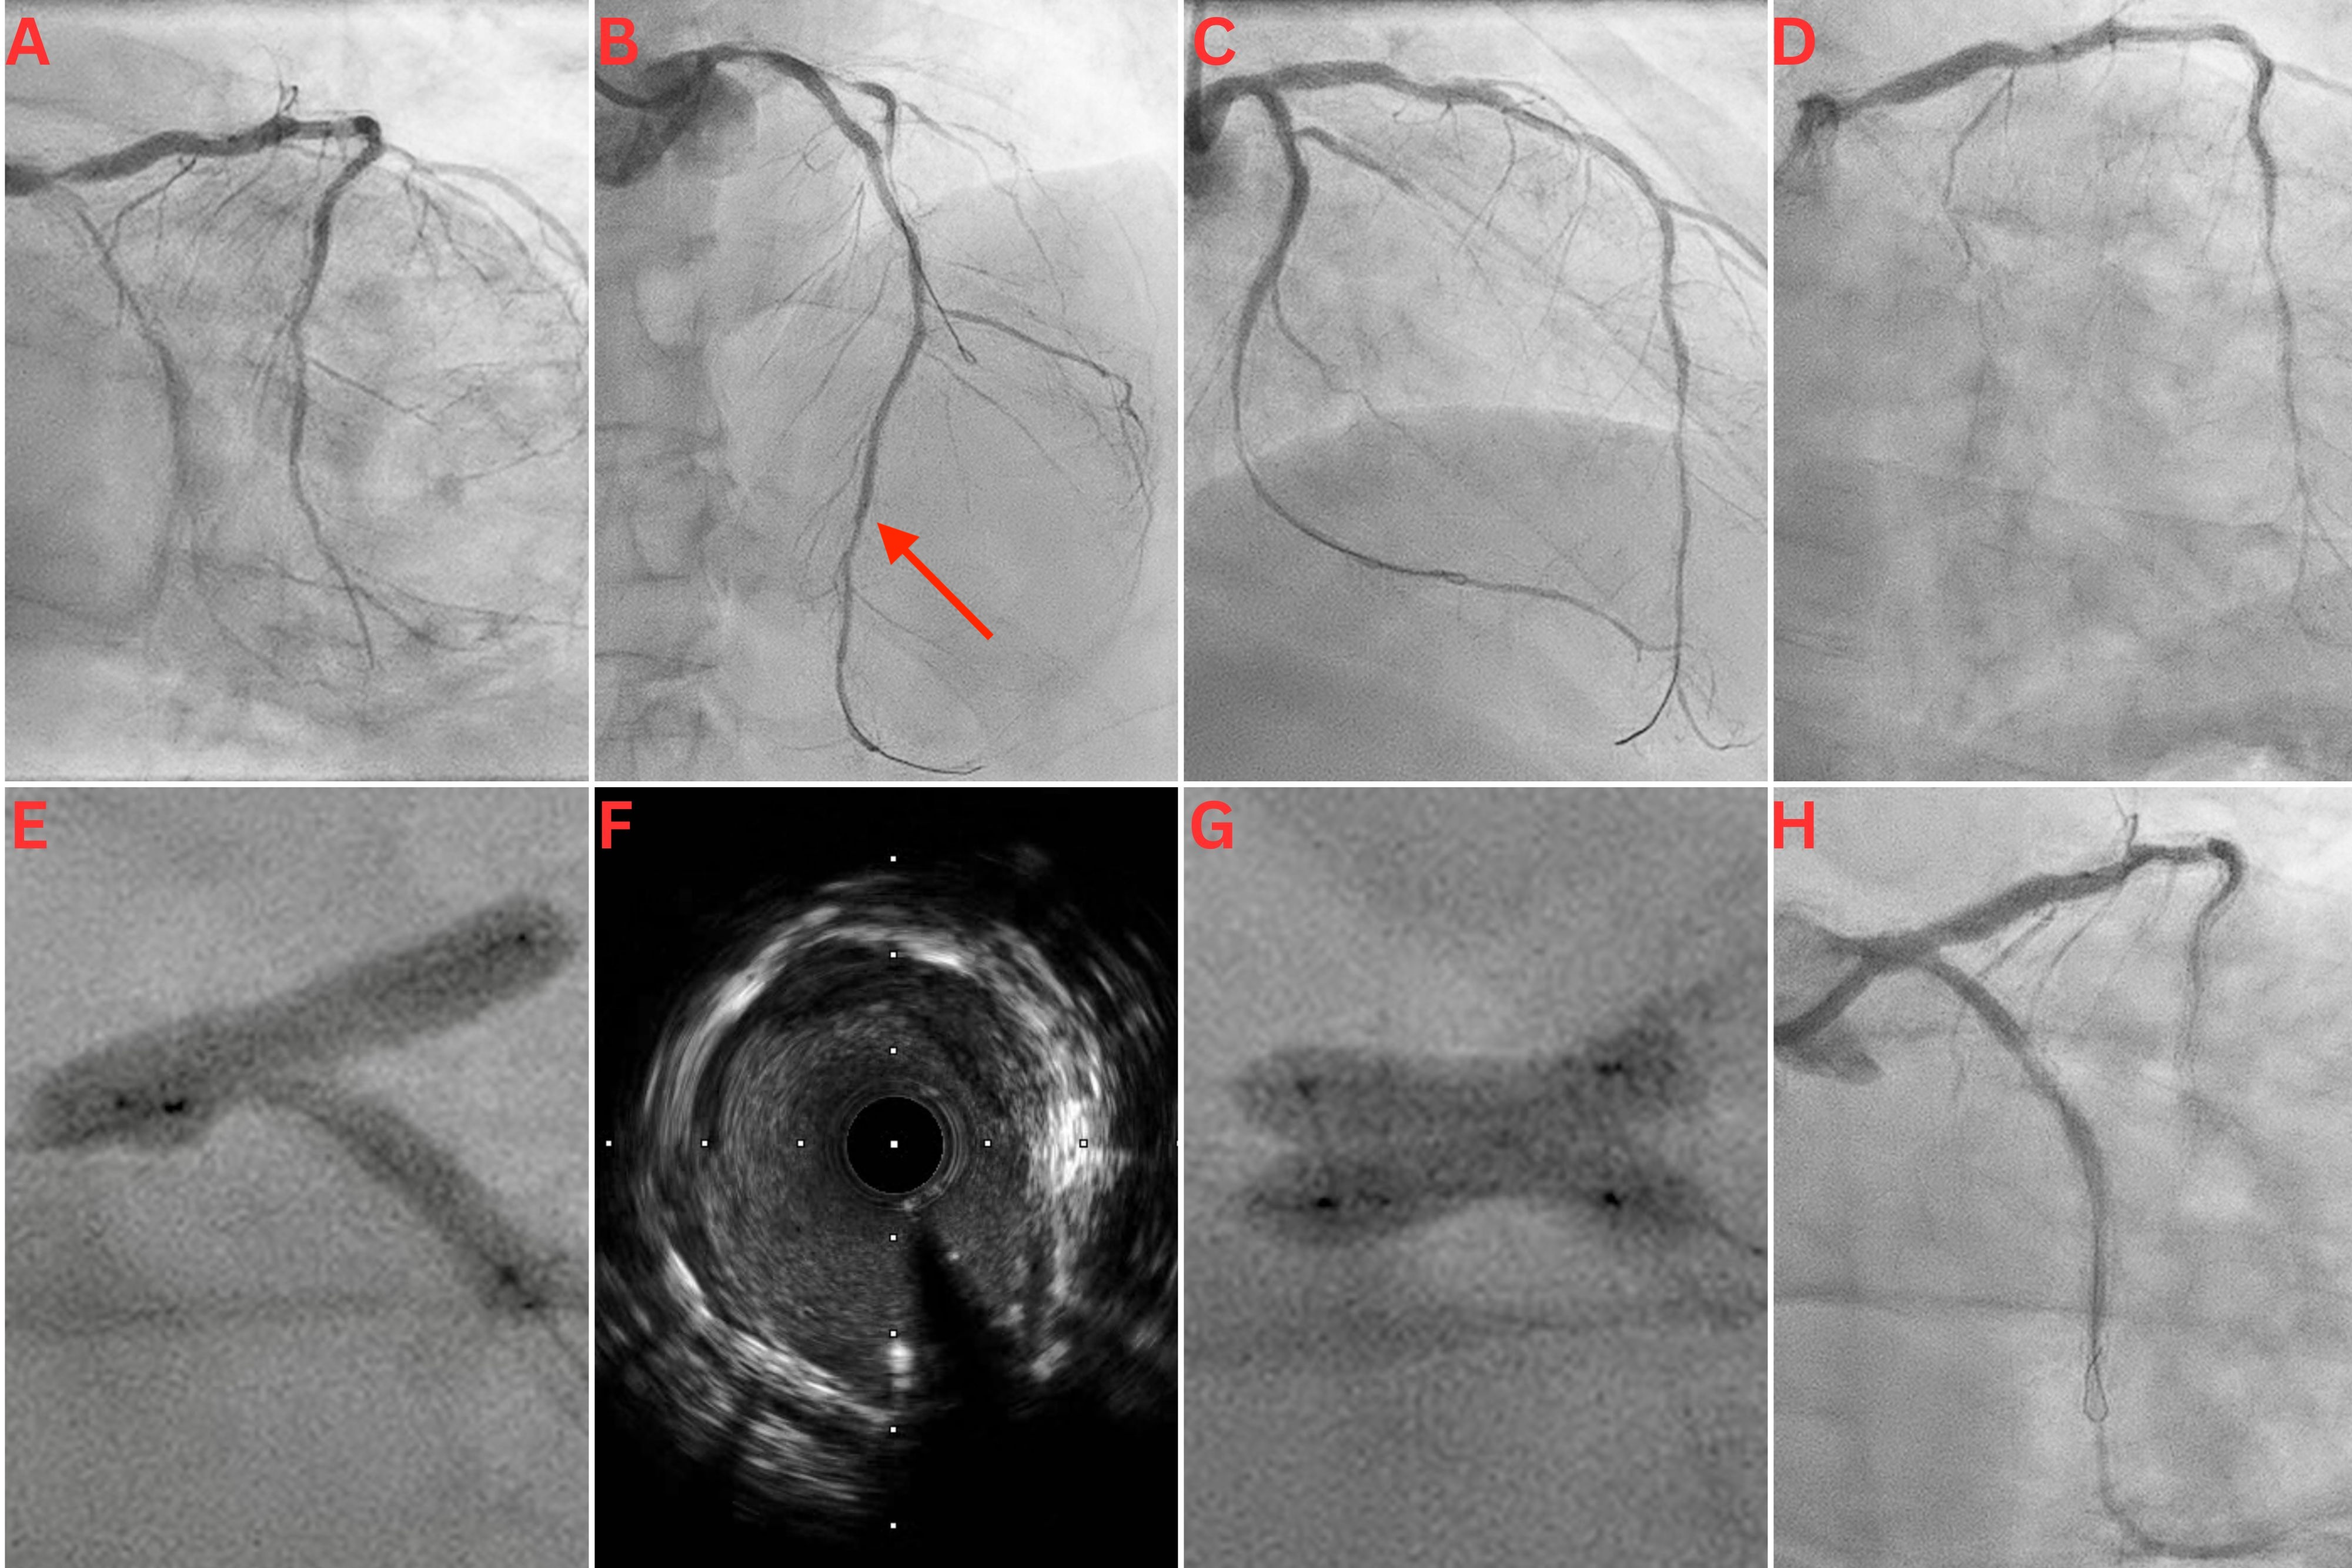

A 65-year-old man with a history of extensive percutaneous coronary intervention (PCI) because of recurrent in-stent restenosis (ISR) presented with a non-ST segment elevation myocardial infarction (NSTEMI). Coronary angiography revealed severe ISR in his left main coronary (LMCA), left anterior descending (LAD), and left circumflex (LCx) arteries (Figure A and B). Intravascular ultrasound (IVUS) revealed an LMCA diameter of 5.5 mm, deep vessel calcification, and severe neo-intimal hyperplasia, with only mild stent underexpansion. IVUS-guided PCI of the LMCA, LAD, and LCx was performed using a scoring balloon, a 5.5-mm noncompliant (NC) balloon in the LMCA, and 4.0 and 3.5-mm Paclitaxel drug-eluting balloons (DEB) in the LAD and LCx, respectively. There was a good final angiographic result following this intervention (Figure C).

The patient represented 5 months later with an NSTEMI. Angiogram revealed critical ISR of the recently treated LMCA bifurcation (Figure D). PCI was performed using NC and cutting balloons, followed by several applications of excimer laser coronary atherectomy (ELCA) in the LMCA, LAD, and LCx. Three-stage kissing balloon inflations (KBI) at the LMCA bifurcation were performed with a 4.0-mm NC balloon in the LAD and a 3.5-mm NC balloon in the LCx. There was significant waisting without complete balloon expansion (Figure E). IVUS showed calcification, stent recoil, and residual neo-intimal hyperplasia (Figure F, Video 1). Following prolonged inflations with 4.0 x 20-mm and 3.5 x 20-mm Paclitaxel DEBs in the LAD and LCx, respectively, two 4.0 x 10-mm OPN NC ultra high-pressure balloons (SIS Medical AG) were used individually for postdilation in both the proximal LCx and LAD; they were each inflated to 40 atm. Finally, KBI was performed in the LMCA/LAD/LCx bifurcation with the 2 OPN balloons to 20 atm each. There was complete balloon expansion with noticeable angiographic improvement (Figure G).

Following ELCA and balloon angioplasty, there was minimal tissue within the stents in either vessel. However, there was significant tissue behind the stent in the LCx, giving the appearance of moderate disease in the mid-LCx on the final angiographic images. Given there was a good minimal luminal area on IVUS, and the patient had a poor response to stents in the past with recurrent ISR, this was accepted as a good final angiographic result at the end of the procedure (Figure H, Video 2). The patient was discharged on dual antiplatelet therapy and colchicine for its antiproliferative effects. He remained well and asymptomatic on review after 6 months.